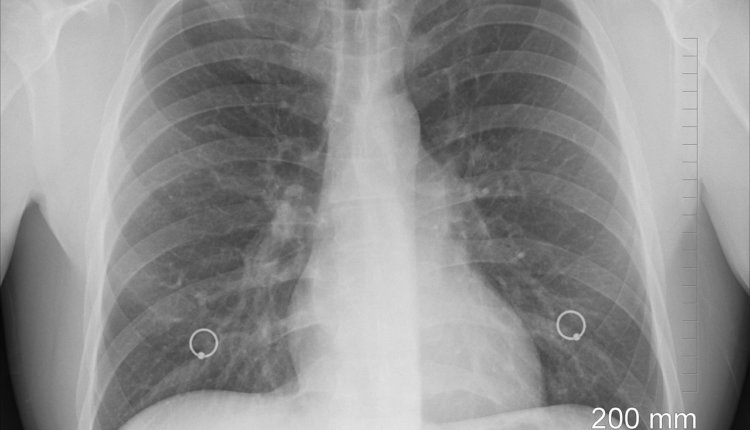

Сульфаты, никель и ванадий: ключевые компоненты загрязнения, вызывающие астму

Исследование, проведённое учёными Гарвардской школы общественного здравоохранения имени Т. Х. Чана, выявило, что определённые компоненты мелкодисперсной взвеси (PM2.5), а именно сульфаты, никель и ванадий, оказывают наибольшее влияние на частоту госпитализаций по поводу астмы при длительном воздействии загрязнённого воздуха.

В отличие от большинства предыдущих работ, которые рассматривали воздействие отдельных загрязнителей или общего состава PM2.5, авторы нового исследования применили алгоритмы машинного обучения для выделения конкретных компонентов в составе загрязняющих веществ. Они обнаружили, что увеличение концентрации никеля, ванадия и сульфатов в воздухе связано с повышением числа госпитализаций по поводу астмы: на 10,6% среди детей и на 8% среди взрослых в возрасте от 19 до 64 лет.

Учёные отмечают, что никель и ванадий образуются при сжигании мазута, используемого в отопительных системах и крупных зданиях, а сульфаты — при сжигании угля. Для снижения их концентрации в воздухе предлагается использовать очистные установки на угольных электростанциях и очищать топливо от металлических загрязнителей.

Результаты исследования подчёркивают необходимость целенаправленного контроля за конкретными загрязнителями в составе PM2.5 для эффективного снижения заболеваемости астмой.